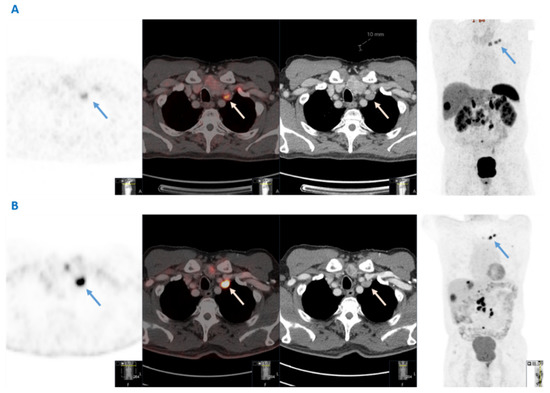

The initial detection of VM in the nine patients identified in this study was made by clinical examination in two patients, conventional CT in two patients and 68Ga-DOTATATE PET-CT in five patients. Overall, in two out of four patients with synchronous VM, the presence of VM itself led to the SI-NET diagnosis. Importantly, all VM lesions were somatostatin receptor positive in this series in subsequent functional imaging. Histopathological confirmation of VM secondary to SI-NET was obtained in five patients for diagnostic purposes through core needle biopsy (n = 3) or surgical resection (n = 2) of the left supraclavicular nodes. 18F-FDG PET-CT was performed in only three patients, in two of whom the VM lesion was FDG positive. The CT scan, 68Ga-DOTATATE PET-CT and 18F-FDG PET-CT imaging of a SI-NET patient with VM are shown in Figure 1.

In addition, G1 and G2 SI-NET patients may also have 18F-FDG-positive tumors initially or may develop 18F-FDG-positive lesions during follow-up, as demonstrated in Figure 1, with important implications for therapy optimization and disease surveillance. Dual functional imaging could probably be considered prior to treatment initiation to delineate tumor somatostatin receptor expression and glycolytic metabolic activity in the context of a personalized treatment strategy at least in G2 patients with Ki67 in the higher levels. Baseline dual-functional imaging assessment in higher grade SI-NETs with advanced tumor burden could be used for the selection of patients requiring PRRT or other systemic treatments as well as the prognostic evaluation of the disease [21]. Therefore, as G2 tumors were more often associated with the presence of VM, dual functional imaging could probably be considered in a subset of SINET patients of higher grade and more advanced disease at baseline, with the aims to accurately define metastatic extent and tumor aggressiveness.

Figure 1. Dual functional imaging of a patient with a G2 small intestinal neuroendocrine neoplasm and Virchow’s node metastases (blue and white arrows), both 68Ga-DOTATATE- and 18F-FDG avid. (A) From left to right: 68Ga-DOTATATE PET; fusion; computed tomography; and maximum intensity projection (MIP) images (B) From left to right: 18F-FDG PET; fusion; computed tomography; and maximum intensity projection (MIP) images.